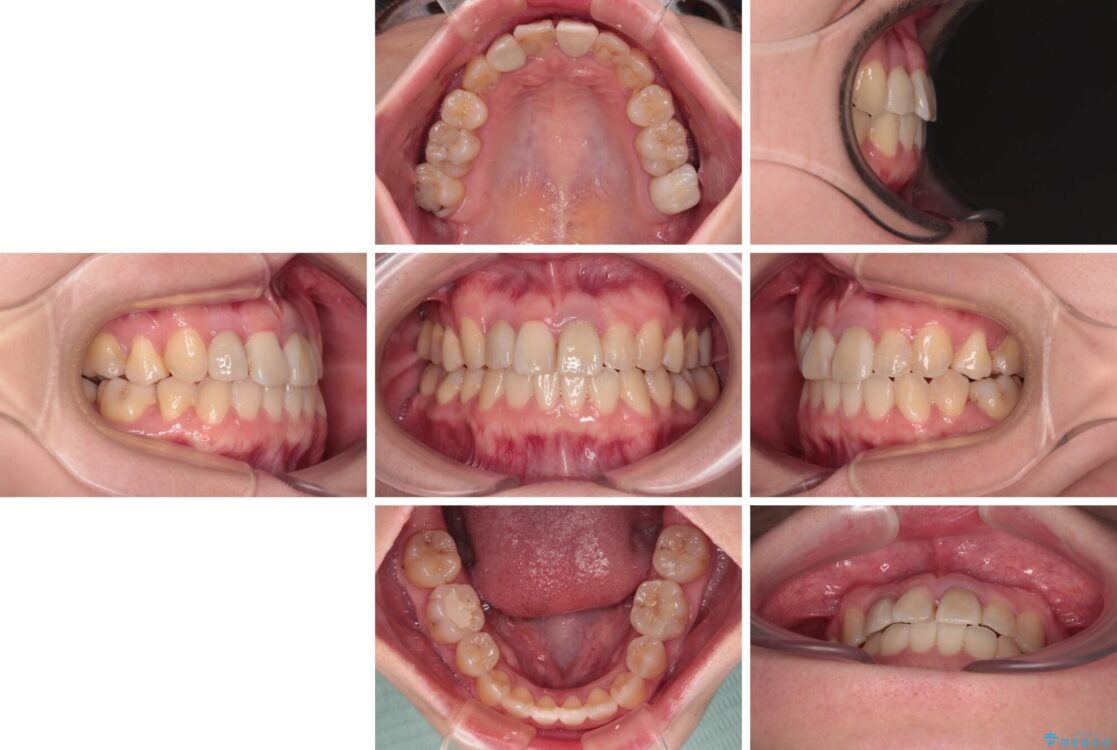

治療後

• 虫歯治療ついでに歯並びの後戻りを改善 インビザラインによる矯正治療 治療後画像